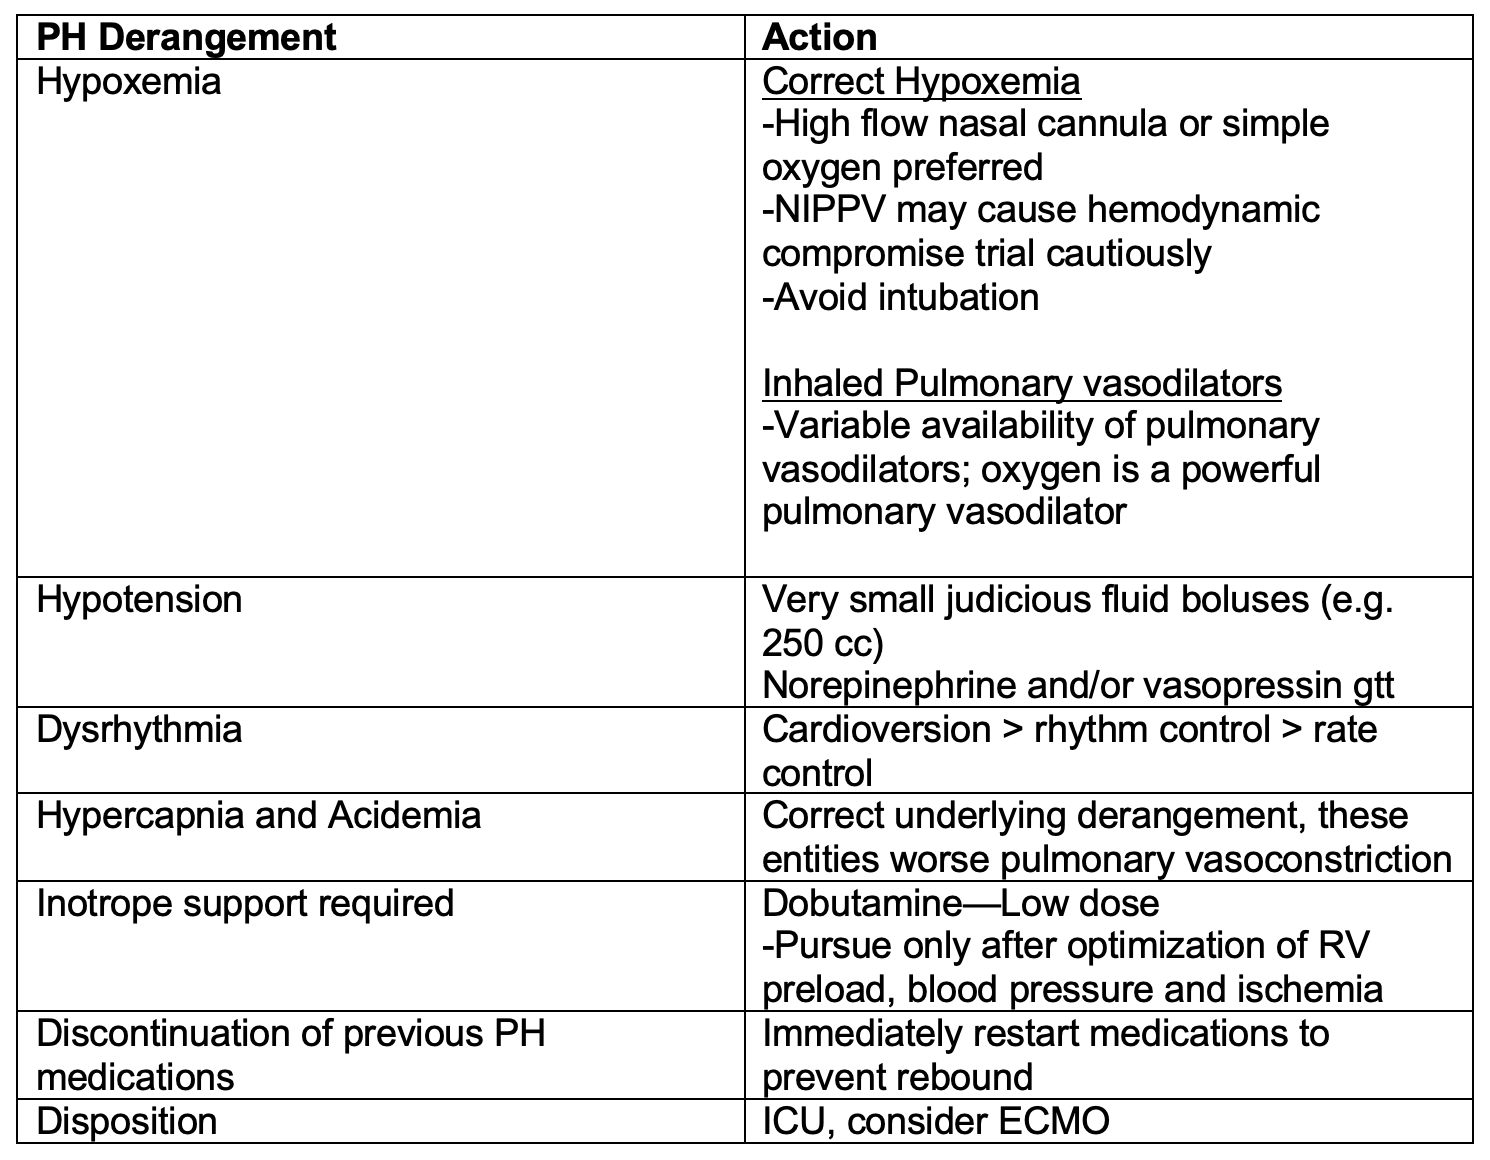

Pulmonary Hypertension Crisis

Patients with PH may present unstable from an acute illness (e.g. sepsis) or become unstable after an intervention (e.g. intubation). The emergency clinician must have an approach to managing the patient with PH who becomes unstable to prevent the deadly cycle of hypotension, worsening pulmonary vascular resistance, RV ischemia worsening cardiac output leading to cardiovascular collapse. Below is a reference table to outline critical actions to take in a pulmonary hypertension crisis.